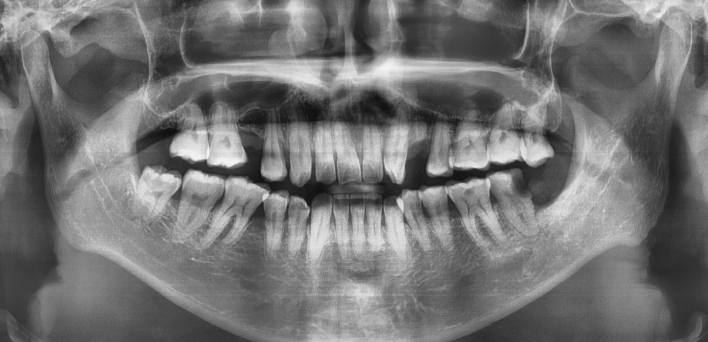

임플란트 케이스

임플란트 Before & After

The seoul dental clinic

치료 기록 더보기버튼

※ 더서울치과의원은 의료법을 준수하며 위 케이스는 실제 환자의 동의를 얻은 사례로 치료 전, 후가 동일한 환경에서 촬영되었습니다.

환자 케이스에 따라 부작용이 발생할 수 있습니다. 이 부분은 의료진의 충분한 상담과 체크를 통해 예방하고 줄일 수 있습니다.

[임플란트 부작용] 수술 후 관리가 소홀할 경우 출혈, 주위염 등의 부작용이 발생할 수 있어 구강 위생을 철저히 유지하고, 정기적인 검진을 통해 상태를 점검하는 것이 중요합니다.